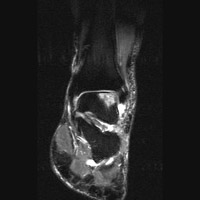

E E | STIR image of the ankle. The region of intermediate signal intensity on the PD image here is seen as bright signal, corresponding to edema. |